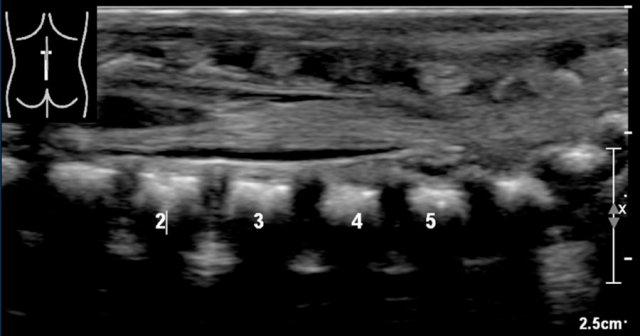

Vị trí của nón tủy

Vị trí bình thường của nón tủy là ở L1.

Nón tủy không được nằm dưới mức L2.

Cách tốt nhất để xác định vị trí của nón tủy là nhận diện khớp thắt lưng-cùng tại góc ưỡn giữa các đốt sống thắt lưng và cùng (mũi tên).

Ở trẻ sơ sinh này, khớp thắt lưng-cùng khó nhận diện hơn do không có góc nhọn rõ ràng.

Các số thứ tự chúng tôi đã đánh dấu có thể không chính xác.

Nếu còn nghi ngờ, hãy chụp ảnh toàn cảnh hoặc ảnh kép của cột sống thắt lưng-cùng và so sánh số đốt sống đếm từ dưới lên với phim X-quang thẳng nghiêng.